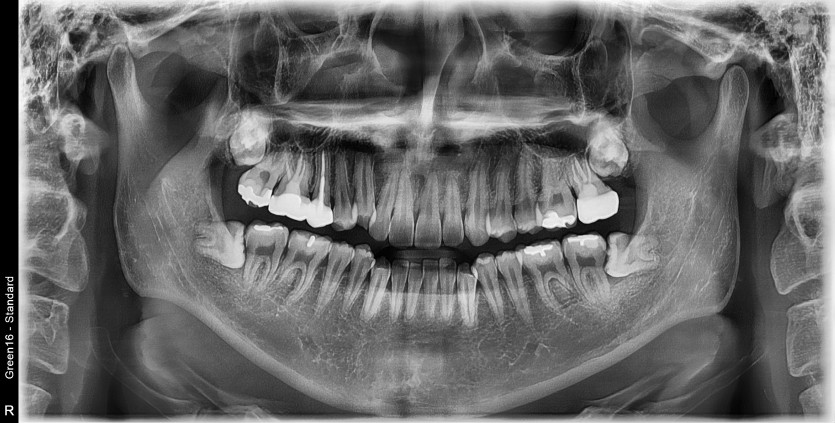

#38 사랑니 발치

구강 외과 전문의가 당일 발치했습니다.